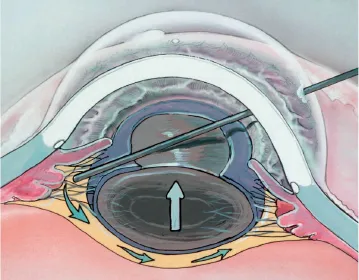

Conduta frente a um GPAF agudo

A) INICIAL:

B) DEFINITIVO